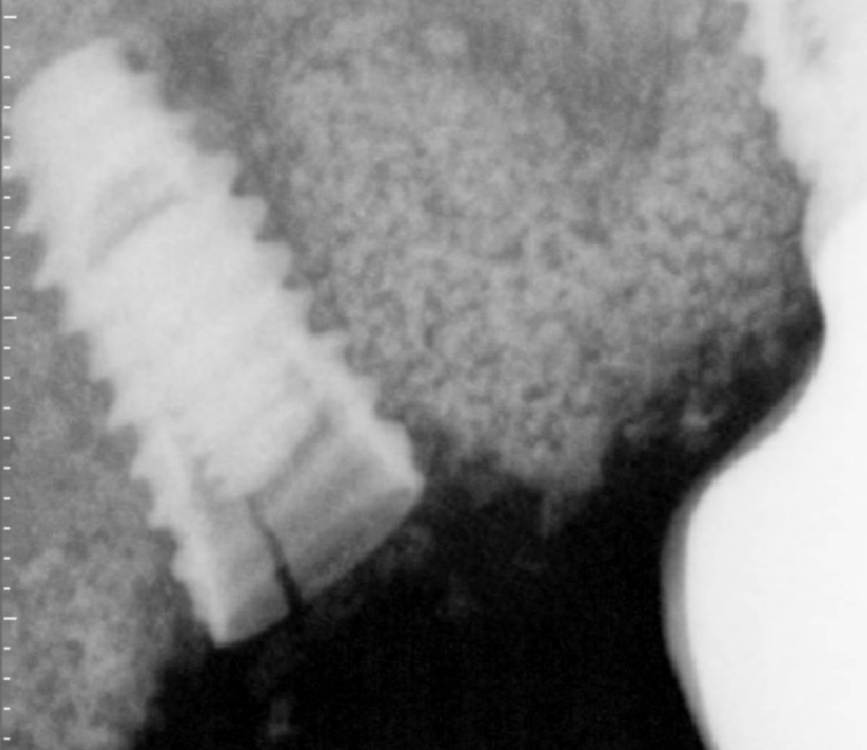

АнтонТЛТ Опубликовано 4 июня, 2021 Поделиться Опубликовано 4 июня, 2021 Жил да был имплантат 3.5мм, прижимался хорошо вместе с поджсаженной костью. Но в один момент ортопед со злобным техником решили его запротезтровать неоригинальным тибейсом в составе цирконевого моста. Имплантату это не понравилось и он решил, что ему пора на покой. И сделал себе харакири. А чтобы не сильно травмировать пациента, было решено удалить винт и имплантат. Затем сразу же поставить имплантат чуть короче и немного потолще. Время работы 50минут с учётом фотографий. 3 Ссылка на комментарий

АнтонТЛТ Опубликовано 4 июня, 2021 Автор Поделиться Опубликовано 4 июня, 2021 1 час назад, Irouil сказал: Винт, насколько я понимаю, удалялся реверсивным сверлом. А чем удалялся сам имплант? Fr-kit neobiotech 1 Ссылка на комментарий